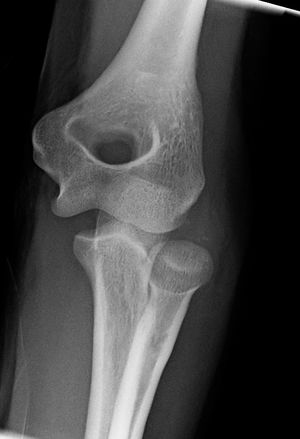

Close-up radiograph, right elbow-joint